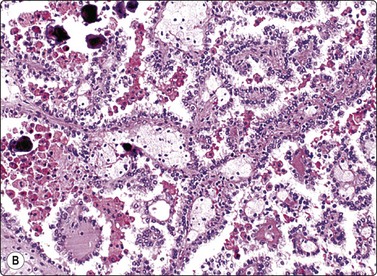

The collecting duct type of renal carcinoma is rare. Smears show small groups and single cells of glandular or intermediate type with malignant nuclear features. A tubular or papillary arrangement may be present. Fragments of fibrous stroma may reflect desmoplasia seen in tissue sections (Fig. 12.22). Metastatic carcinoma, papillary RCC and TCC should be included in the differential diagnosis.84-86

image image

Fig. 12.22 Collecting duct RCC

(A) Tissue fragment of obviously malignant epithelial cells resembling TCC; note stromal fragments representing desmoplasia (DQ, HP); (B) Corresponding tissue section (CNB, H&E, IP).